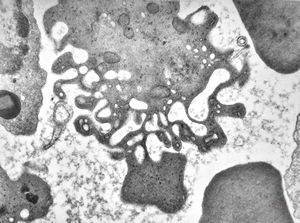

M,33y. | blood - hairy cell leukemia- ribosome-lamella complexin tricholeukocyte

M,41y. | hairy cell leukemia - spleen - ribosome-lamella complex in tricholeukocyte